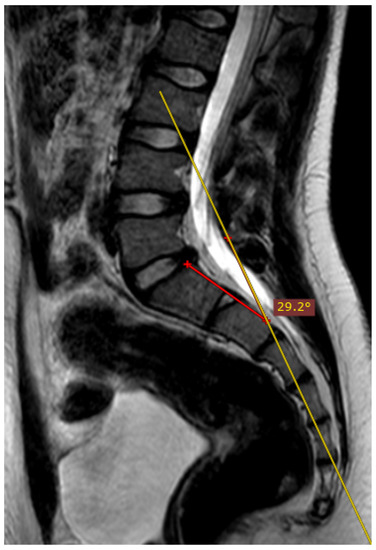

The deviation angles were measured on T2-weighted sequence slices obtained in the sagittal plane, as shown in Figure 1. Figure 2, presented below, shows the interrelationship of the three sequences of the same examination (as shown in Figure 1) that were used in this study. The RadiAnt DICOM Viewer was used to take measurements. All examinations were analyzed by two independent researchers in a blind study. The final results of the measurements were averaged to obtain a single deviation angle corresponding to each examination.

Figure 1.

The measured deviation angle equals 5.3 degrees (group 2). The red line is the fully correct line drawn between the posterior edges of the S1 and S2 vertebrae. The yellow line marks the actual plane in which the slices were acquired.

Overall, 20% (n = 35) of the examinations included in the study were performed perfectly correctly considering the technical aspect of the MRI procedure. The examination was defined as fully correct if the deviation angle measured by all of the researchers equaled 0 degrees (Figure 4). The median deviation angle was equal to 5.7 degrees. The maximal deviation angle measured was 29.2 degrees (Figure 5). The ICC (2, 2) was computed as 0.9960 (95% CI [0.9945, 0.9970]), which indicates excellent reliability between the researchers when measuring the deviation angle. Additionally, Figure 6 represents a Bland-Altman diagram with the limits of 95% agreement stated. The results of the division into quartiles due to the deviation angle measurements of all the examinations are shown in Table 1. The obtained division was considered to be valid for the whole study, and on its basis the analysis of the subsequent parts of the study was performed.

Figure 5.

The measured deviation angle equals 29.2 degrees (group 4), T2-weighted sequence. The red line is the fully correct line drawn between the posterior edges of the S1 and S2 vertebrae. The yellow line marks the actual plane in which the slices were acquired.